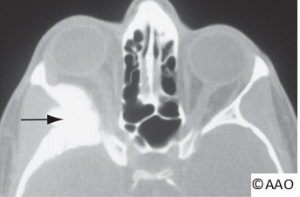

Neuroimaging studies should be performed for patients suspected of having the Foster Kennedy syndrome (e.g., head and orbital CT or MRI with and without contrast).

- Atypical cases should undergo consideration for neuroimaging (CT and MRI) to rule out intracranial mass, optic nerve enhancement